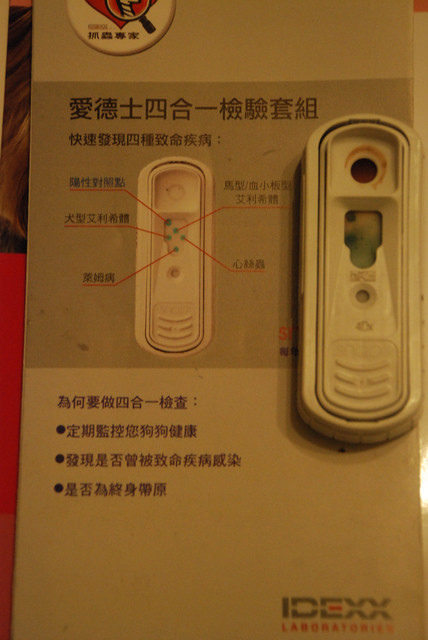

另外做了血檢與四合一檢查。

驗出來有愛麗絲體,另外血檢的狀況是可以接受的正常狀況,除了血紅素的不足、白血球的輕微異常,其他都還好。